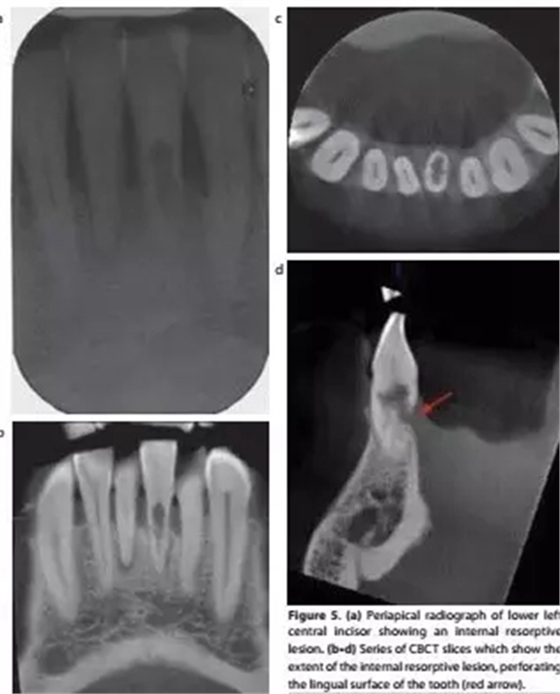

a-根尖片顯示31牙根吸收;b,c,d-對31的CBCT掃描清楚顯示內(nèi)吸收范圍和程度,舌側(cè)牙根已穿通;

對于牙根吸收的情況,CBCT能反映病損來源、位置和進(jìn)展程度,有助于治療方案的制定。例如外吸收一般只能通過手術(shù)進(jìn)行干預(yù),而內(nèi)吸收則需要根據(jù)程度來判斷保留價(jià)值。